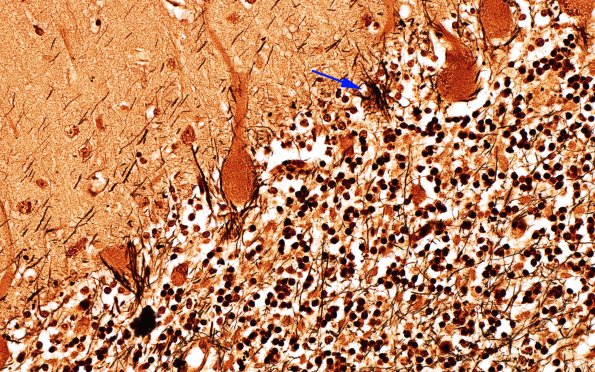

Occasional Purkinje neuron loss is identified by empty baskets of fibers (arrow) originally surrounding intact neurons such as those adjacent in this image. (Bielschowsky)